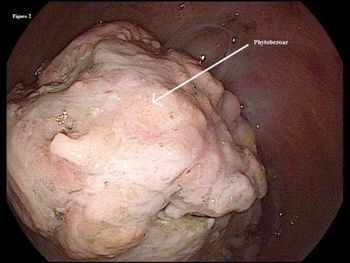

Here: a close-up look at one cause of upper GI bleeds, as well as bezoars, stromal tumor, appendicolith, and Kaposi sarcoma.